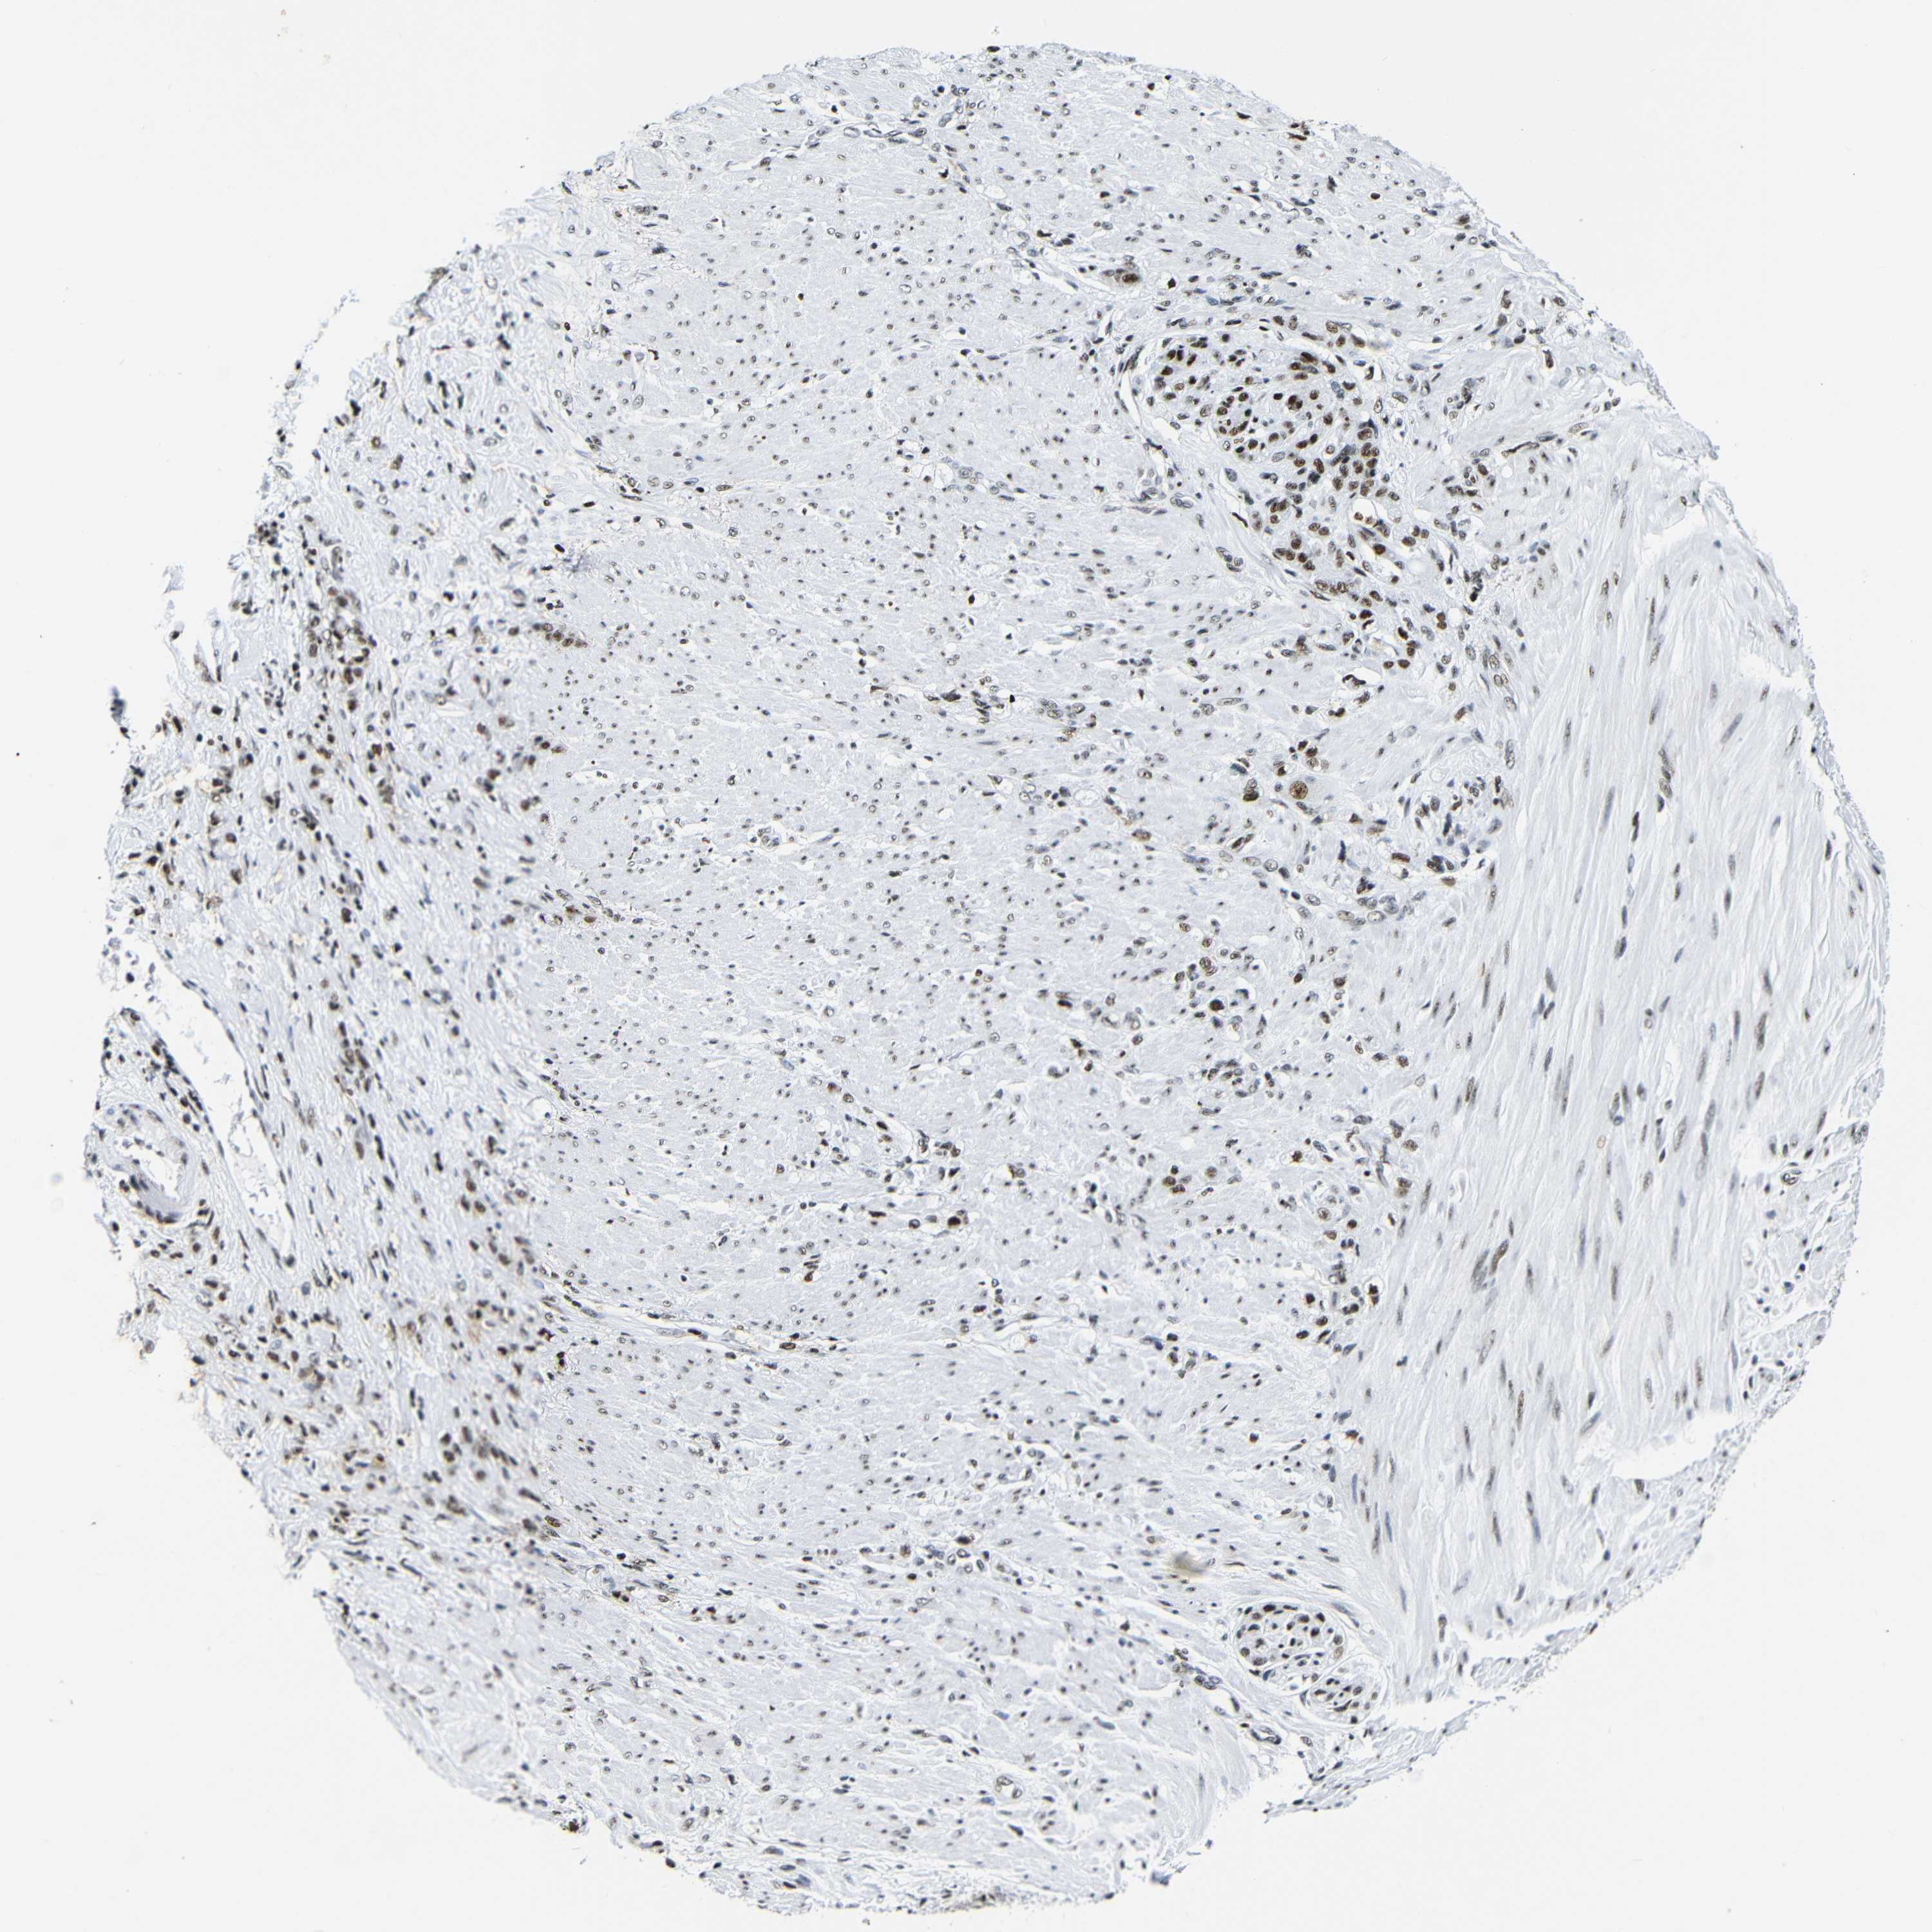

STOMACH CANCER - Protein expressioni

A mouse-over function shows sample information and annotation data. Click on an image to view it in a full screen mode. Samples can be filtered based on level of antibody staining by selecting one or several of the following categories: high, medium, low and not detected. The assay and annotation is described here.

Antibody stainingi

Antibody staining in the annotated cell types in the current human tissue is reported as not detected, low, medium, or high, based on conventional immunohistochemistry profiling in selected tissues. This score is based on the combination of the staining intensity and fraction of stained cells.

Each image is clickable and will lead to virtual microscopy that enables deeper exploration of all samples and also displays staining intensity scores, fraction scores and subcellular localization as well as patient and tissue information for each sample.

Antibody HPA061301

Antibody CAB013073

Staining

High

Medium

Low

Not detected

Intensity

Strong

Moderate

Weak

Negative

Quantity

>75%

75%-25%

<25%

None

Location

Nuclear

Cytoplasmic/membranous

Cytoplasmic/membranous,nuclear

Adenocarcinoma, NOS

Adenocarcinoma, High grade